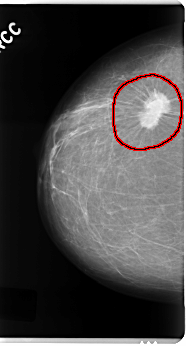

C_0121_1.RIGHT_CC

FILE: C_0121_1.RIGHT_CC.OVERLAY

TOTAL_ABNORMALITIES 1

ABNORMALITY 1

LESION_TYPE MASS SHAPE IRREGULAR MARGINS SPICULATED

ASSESSMENT 5

SUBTLETY 5

PATHOLOGY MALIGNANT

TOTAL_OUTLINES 1

BOUNDARY